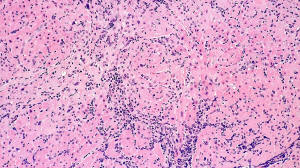

Figure D. CD20 IHC staining

Histology: H&E section (Figure A) of the myocardial tissue shows foci of perivascular mononuclear cell infiltration with some associated myocardial damage consistent with moderate acute cellular rejection (grade 2R) (ISHLT 1990 Grade 3A).  Special immunohistochemistry staining for CD3 and CD68 (Figure B and Figure C) show a predominant population of T cells and macrophages. Special stating for CD20 shows only a few scattered B cells (Figure D).